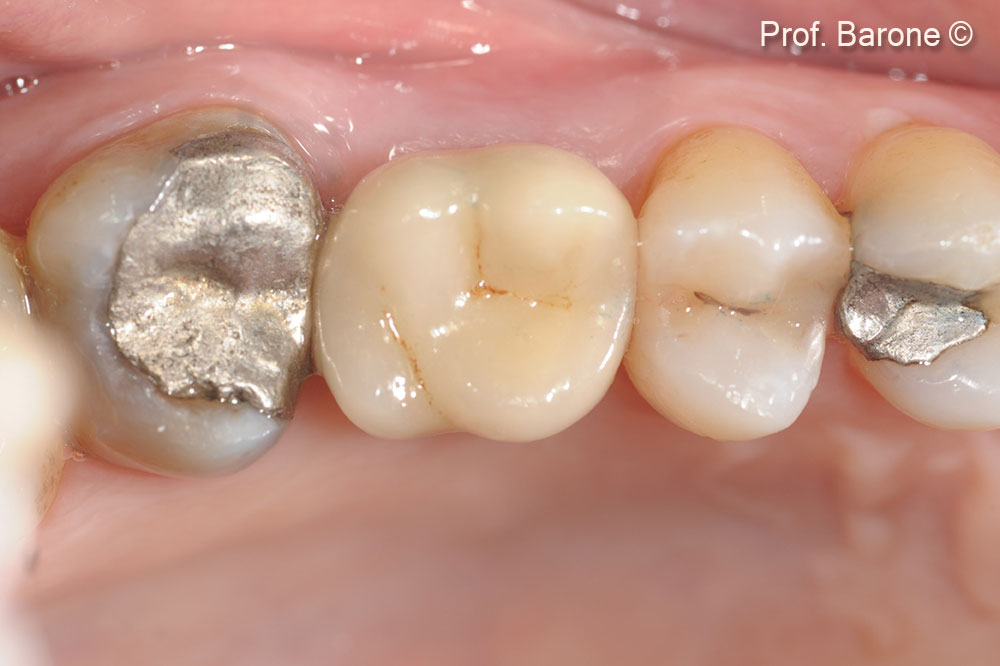

Occlusal view. Tooth n 26